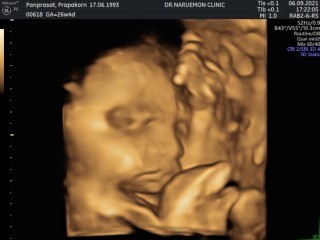

ทีมลูกสาวจ้า (ท้องแรก)